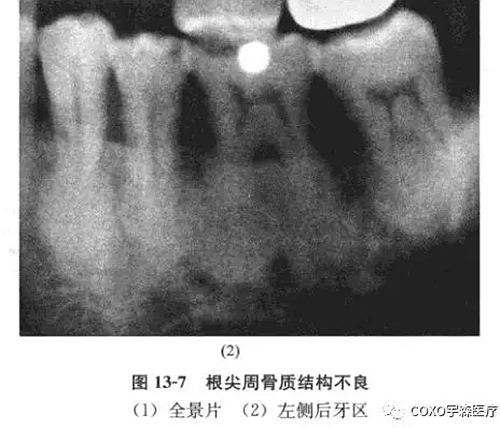

病例:男性,71歲,雙側(cè)下頜骨后牙區(qū)反復腫脹2年余,曾在當?shù)蒯t(yī)院口腔科行5]根管治療術,效果不明顯,而將5]拔除,拔牙創(chuàng)一直未愈并伴疼痛,故轉(zhuǎn)我院就診。

x線片示:雙側(cè)后牙區(qū)高密度陰影(圖13-7),初步診斷:雙側(cè)后牙區(qū)根尖周骨質(zhì)結(jié)構(gòu)異常,伴感染,收入院。

全麻再加局麻,拔除64-45 64]牙根肥大,成骨樣物質(zhì),[45根尖肥大,有牙骨質(zhì)樣物質(zhì),[4拔牙創(chuàng)有膿液。64-45之拔牙創(chuàng)刮治,氯霉素沖洗,置碘仿紗條,縫合。病理診斷:雙側(cè)上下頜骨根尖周牙骨質(zhì)增生,拔牙創(chuàng)炎性肉芽組織,伴表面上皮增生。

分析與評述

根尖周炎與根尖周牙骨質(zhì)結(jié)構(gòu)不良的主要鑒別是前者為牙髓炎性壞死引起,而后者的演變有一個有趣的過程, 線片表現(xiàn)出三個不同時期,無論何期牙髓均為活髓,根尖周病變中鈣化物可能完全是牙骨質(zhì),也可能為骨質(zhì),或二者皆有。

其演變過程:正常牙槽骨-纖維變性-致密的、非典型的再礦化。

初期階段(纖維變性或溶骨階段)其特征是根尖牙周間隙中成纖維細胞和膠原纖維增生,造成硬骨板及其周圍的松質(zhì)骨吸收(圖13-8),不同于根尖周炎或根尖周囊腫,新生物是無炎癥的,神經(jīng)和血管在根管的進出是無影響的。

中期(早期的根尖周牙骨質(zhì)結(jié)構(gòu)不良)大多數(shù)在活髓牙的根端,表現(xiàn)為孤立性病變或多發(fā)性病變,通常無自覺癥狀,極少數(shù)顯示輕度頜骨膨脹,x線片上顯示鈣化灶時,可認為病變是成熟的中間期,隨著鈣化成分逐漸增多及出現(xiàn)融合,病變的密度亦增高,不同病變及不同患者間鈣化灶的大小、形狀、數(shù)目等變化較大,不引起牙根吸收。

晚期(成熟的根尖周牙骨質(zhì)結(jié)構(gòu)不良)病變在活髓牙根端,孤立或多發(fā)性,x線片密度高,影像均勻一致,大多數(shù)為圓形或卵圓形,但偶爾為不規(guī)則形,組織學上幾乎完全由不同比例的致密牙骨質(zhì)和骨組織形成,腔隙或血管間隙很少。

筆者所報道之病例,根尖周牙骨質(zhì)結(jié)構(gòu)不良的表現(xiàn)各階段都有,但以成熟階段為主,牙根已變成圓形或橢圓形,有時,病變擴大,致密質(zhì)骨膨脹,粘膜潰爛,繼發(fā)感染,也可逆行性引起牙髓炎癥、甚至壞死,該患者就出現(xiàn)過因牙痛就診行根管治療術的經(jīng)歷。